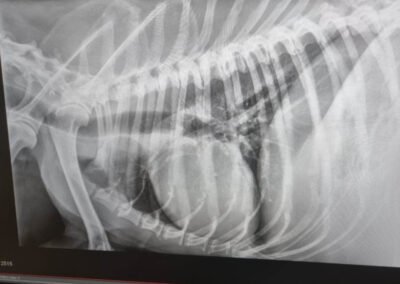

Die Untersuchungen beim Tierarzt haben leider ergeben, dass er einen Milztumor hat und der Krebs bei Dedo bereits so weit fortgeschritten ist, dass eine Operation keinen Sinn mehr ergeben würde. Die Narkose wäre für ihn ein zu großes Risiko, und wir wollen ihm unnötiges Leiden ersparen. Stattdessen haben wir beschlossen, Dedo seine letzten Tage, Wochen oder Monate so angenehm wie möglich zu gestalten. Dedo darf nun bei unserer Tierschützerin vor Ort im Zwinger leben, da er das Leben draußen gewohnt ist und drinnen nicht bleiben möchte. Sie sorgt liebevoll für ihn und kocht ihm sogar seine Mahlzeiten selbst – eine kleine Freude, die ihm in dieser schweren Zeit geblieben ist. Bitte helft uns, Dedo die letzten Momente seines Lebens so schön wie möglich zu machen. Eine Futter- oder Medizinpatenschaft würde uns sehr helfen, damit wir Dedo in seiner letzten Zeit angemessen versorgen können.